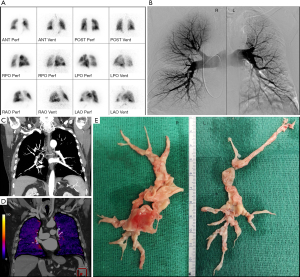

V/Q scanning is highly sensitive (96% to 97.4%) in detecting perfusion abnormalities and with a negative predictive value of nearly 100%, a normal V/Q scan excludes the diagnosis of CTEPH (31). It is therefore currently considered the “gold standard” screening method for CTEPH (Figure 4A). However, the non-specificity of this modality requires additional diagnostic imaging in case of mismatched perfusion deficits to definitively diagnose CTEPH.

Catheter-based pulmonary angiography and right heart catheterization

Catheter-based pulmonary angiography has been considered the “gold standard” for imaging in the evaluation of CTEPH. When combined with right heart catherization, it can confirm the presence of CTEPH to the level of subsegmental vessels, exclude other possible diagnoses, accurately localize or “map out” lesions in the determination of surgical accessibility, and evaluate pulmonary hemodynamics and right heart function (2,32). Characteristic pulmonary angiographic findings suggestive of CTEPH include webs or bands, intimal irregularities, pouch defects, abrupt vascular narrowing, and complete obstruction of pulmonary arteries (Figure 4B) (32).

CTPA

CTPA can be used to assess operability as it can provide detailed structural information including endovascular thrombi, vascular wall thickness, intraluminal fibrous bands or webs, stenosis and bronchial artery collateral circulation (Figure 4C) (30). It may also reveal a mosaic perfusion pattern of the pulmonary parenchyma, suggesting CTEPH. Additional benefits are the assessment of possible underlying parenchymal lung and mediastinal disease and the detection of other pulmonary vessel disorders that may present with perfusion defects on V/Q lung scanning such as pulmonary artery sarcoma, pulmonary veno-occlusive disease or fibrosing mediastinitis (2). However, difficulties with this imaging modality relate to the interpretive expertise required and the lower sensitivity for detecting CTEPD in segmental and subsegmental vessels (33,34).

Next to right heart catheterization to obtain the hemodynamic confirmation of CTEPH, as presented in Figure 3, many CTEPH centers have in the last decade used a combination of catheter based pulmonary angiography and CTPA to obtain the benefits of both imaging techniques to optimally diagnose and assess the operability of CTEPH. Elevated PAP on right heart catheterization with negative findings on pulmonary angiography and CTPA, exclude CTEPH, but not other forms of PH (for example, pulmonary arterial hypertension). On the other hand, normal PAP on right heart catheterization but positive findings on pulmonary angiography and/or CTPA may indicate CTEPD, without PH. Figure 4 illustrates these different imaging modalities for a single patient. This traditional imaging workup has however some inherent disadvantages:

A novel approach whereby one imaging study is performed that can provide qualitative and quantitative assessment of pulmonary perfusion, high spatial resolution assessment of the pulmonary arteries and coronary arteries, and morphologic and quantitative assessment of the heart, all with lower radiation exposure and overall cost, is a great desire of every multidisciplinary CTEPH team. A single ECG-gated dual energy CTPA and coronary CT angiography exam was recently proposed by Kligerman and Hsiao as such a strategy (36). Although this strategy provides a promising single imaging study for screening and operability assessment with lower radiation exposure and costs than current practice, it is not yet researched thoroughly nor validated for this purpose. Moreover, also other emerging imaging techniques may be considered in combination with a coronary CT angiography exam. As such, the recently published Pulmonary Vascular Research Institute (PVRI) Diagnostic algorithm for PH includes CT-lung subtraction iodine mapping (CT-LSIM) (Figure 4D), SPECT and/or MRI perfusion (30).